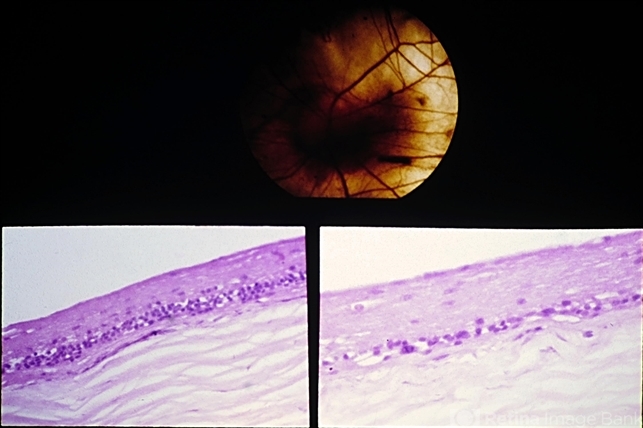

- Unit 09 Pathology of the Retina

- choroideremia, retinal pigment epithelium, sclera

- Choroideremia. There is total loss of the choroid and retinal pigment epithelium except for a small area around the optic disc. Sections through the degenerated area show absence of the choroid and retinal pigment epithelium, and the inner nuclear layer of the retina is in juxtaposition to the sclera (lower view). (Courtesy of Clement McCulloch, M.D. )